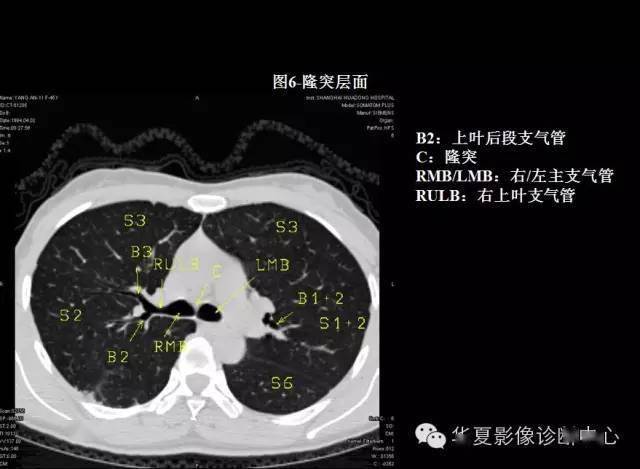

本文来源:华夏影像诊断中心 掌握肺部疾病ct,快速学好肺部感染ct,so